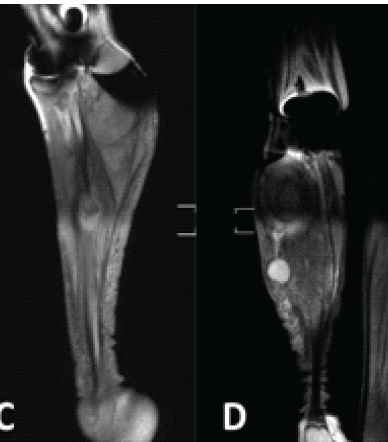

Solitary Diaphyseal Langerhans Cell Histiocytosis of Femur in an Infant – A Case Report

Kavin Sathish , T. Shenbagavalli , S. Chockalingam , P. R. Ramasamy ………………………………p.199-204